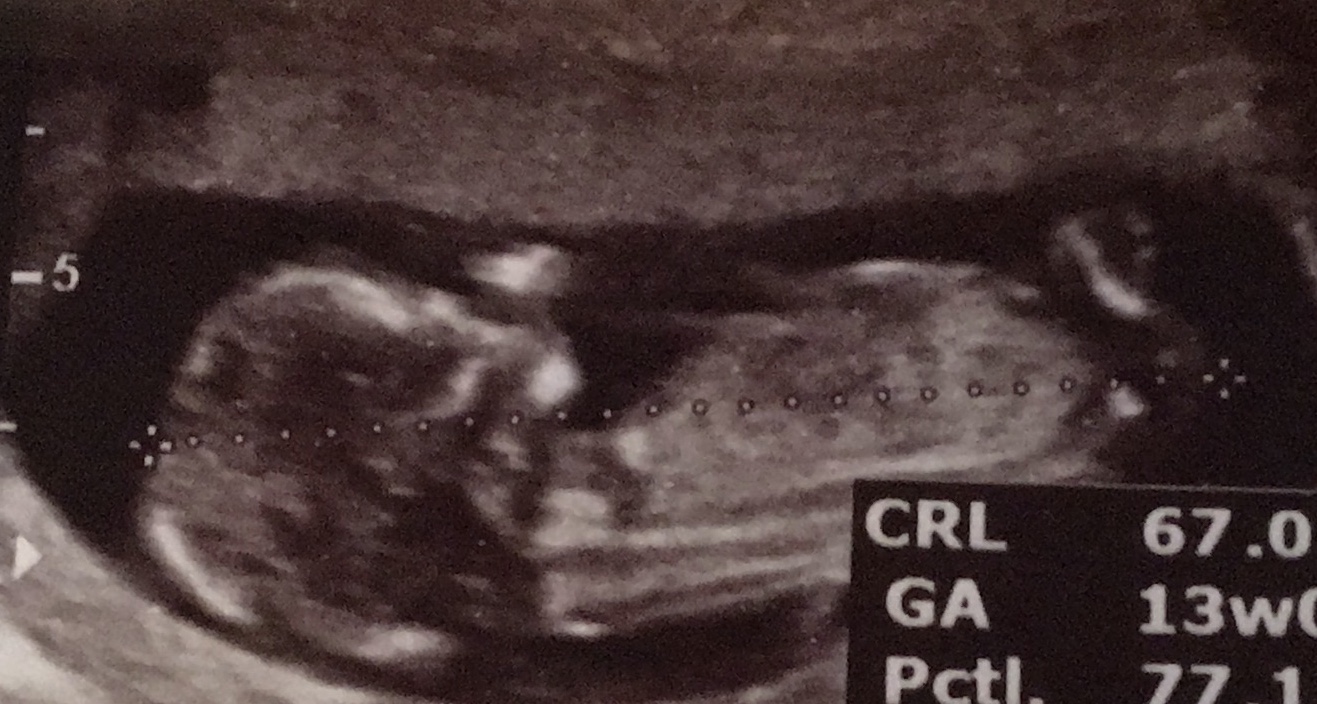

فنچول داشت انگشتشو میخورد😍😁

زیاد زاویش مثل عکس اسی خوب نیست..واضح نیست ولی انگار دختره ..ولی بازم مشخص نیست اونجوری لولهاش